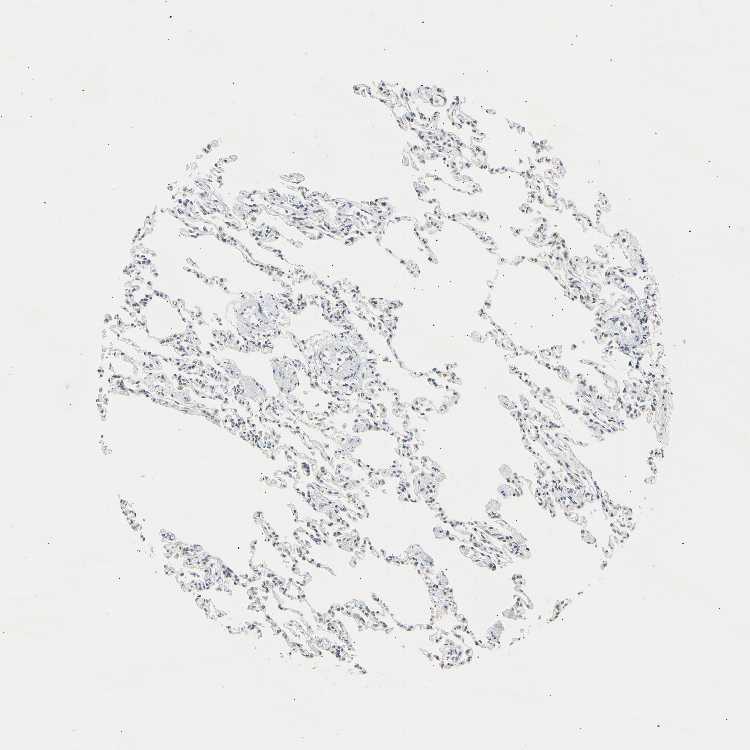

LUNG - Antibody stainingi

Antibody staining in the annotated cell types in the current human tissue is reported as not detected, low, medium, or high, based on conventional immunohistochemistry profiling in selected tissues. This score is based on the combination of the staining intensity and fraction of stained cells.

Each image is clickable and will lead to virtual microscopy that enables deeper exploration of all samples and also displays staining intensity scores, fraction scores and subcellular localization as well as patient and tissue information for each sample.

Antibody HPA008751Antibody CAB005227

Alveolar cells -Not detected

Alveolar cells type I Medium-

Alveolar cells type II Medium-

Endothelial cells Not detected-

Macrophages MediumLow